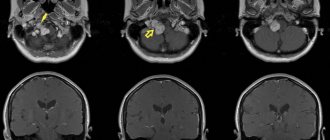

Рекомендуется консультация нейрохирурга, магнитно-резонансная томография забрюшинного пространства.